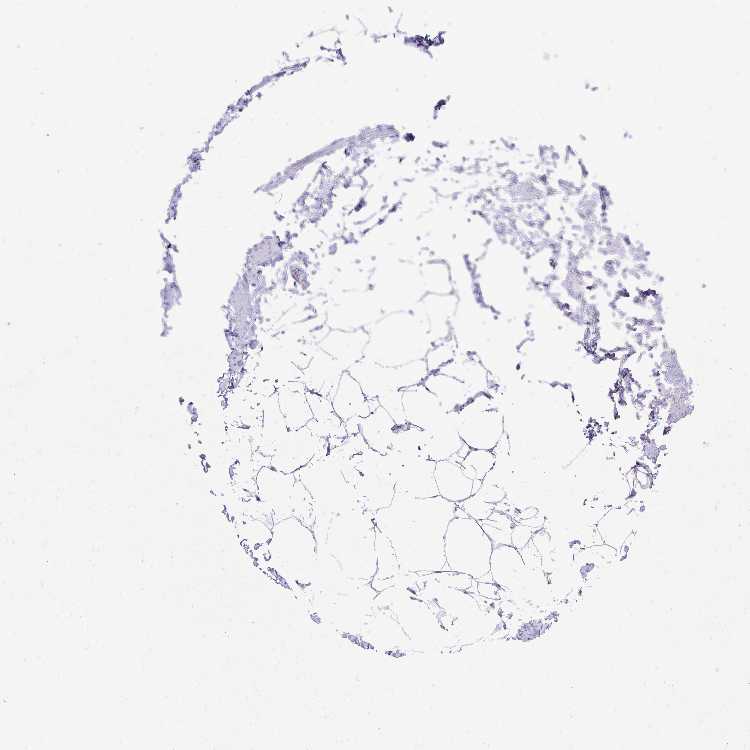

SOFT TISSUE 2 - Antibody stainingi

Antibody staining in the annotated cell types in the current human tissue is reported as not detected, low, medium, or high, based on conventional immunohistochemistry profiling in selected tissues. This score is based on the combination of the staining intensity and fraction of stained cells.

Each image is clickable and will lead to virtual microscopy that enables deeper exploration of all samples and also displays staining intensity scores, fraction scores and subcellular localization as well as patient and tissue information for each sample.

Antibody HPA062890

Fibroblasts Not detected

Peripheral nerve Not detected